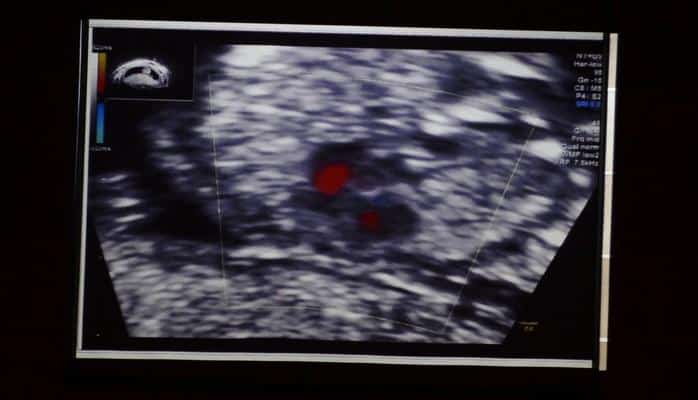

Затем состоялась монолекция радиолога Азера Фараджа.